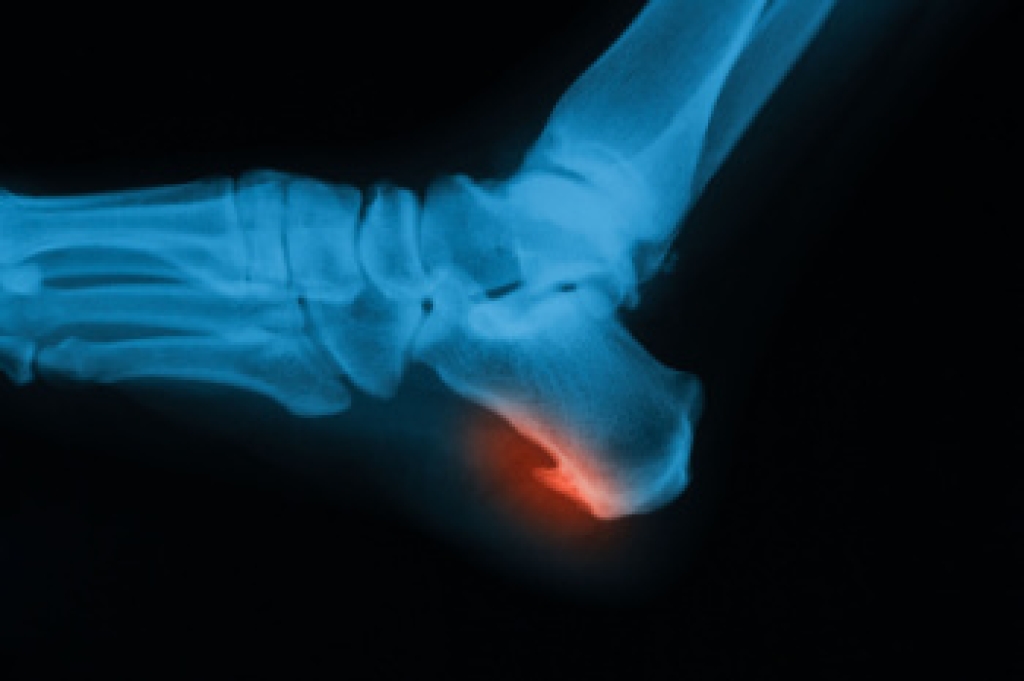

Although most people try to avoid foot trauma such as banging, stubbing, or dropping heavy objects on their feet, the unfortunate fact is that it is a common occurrence. Given the fact that toes are positioned in front of the feet, they typically sustain the brunt of such trauma. When trauma occurs to a toe, the result can be a painful break (fracture).

Symptoms of a Broken Toe

- Throbbing pain

- Swelling

- Bruising on the skin and toenail

- The inability to move the toe

- Toe appears crooked or disfigured

- Tingling or numbness in the toe